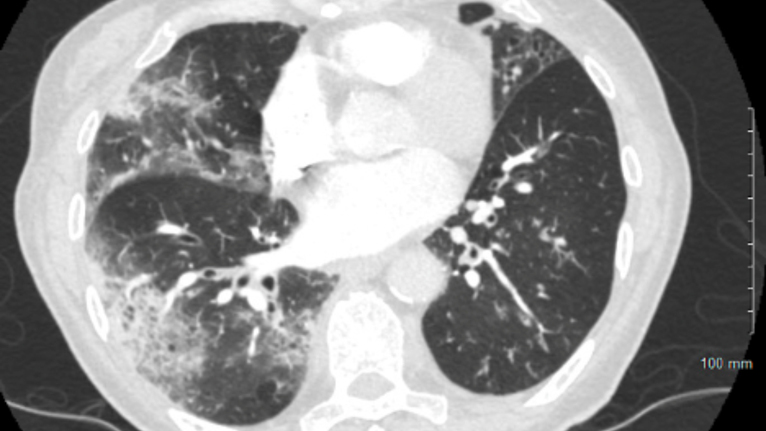

COVID-19 Lung X-Ray - 1 - Lung Damage

Figure 3 – CT chest showing multifocal ground glass opacities with intermixed consolidation from COVID-19 bronchopneumonia.